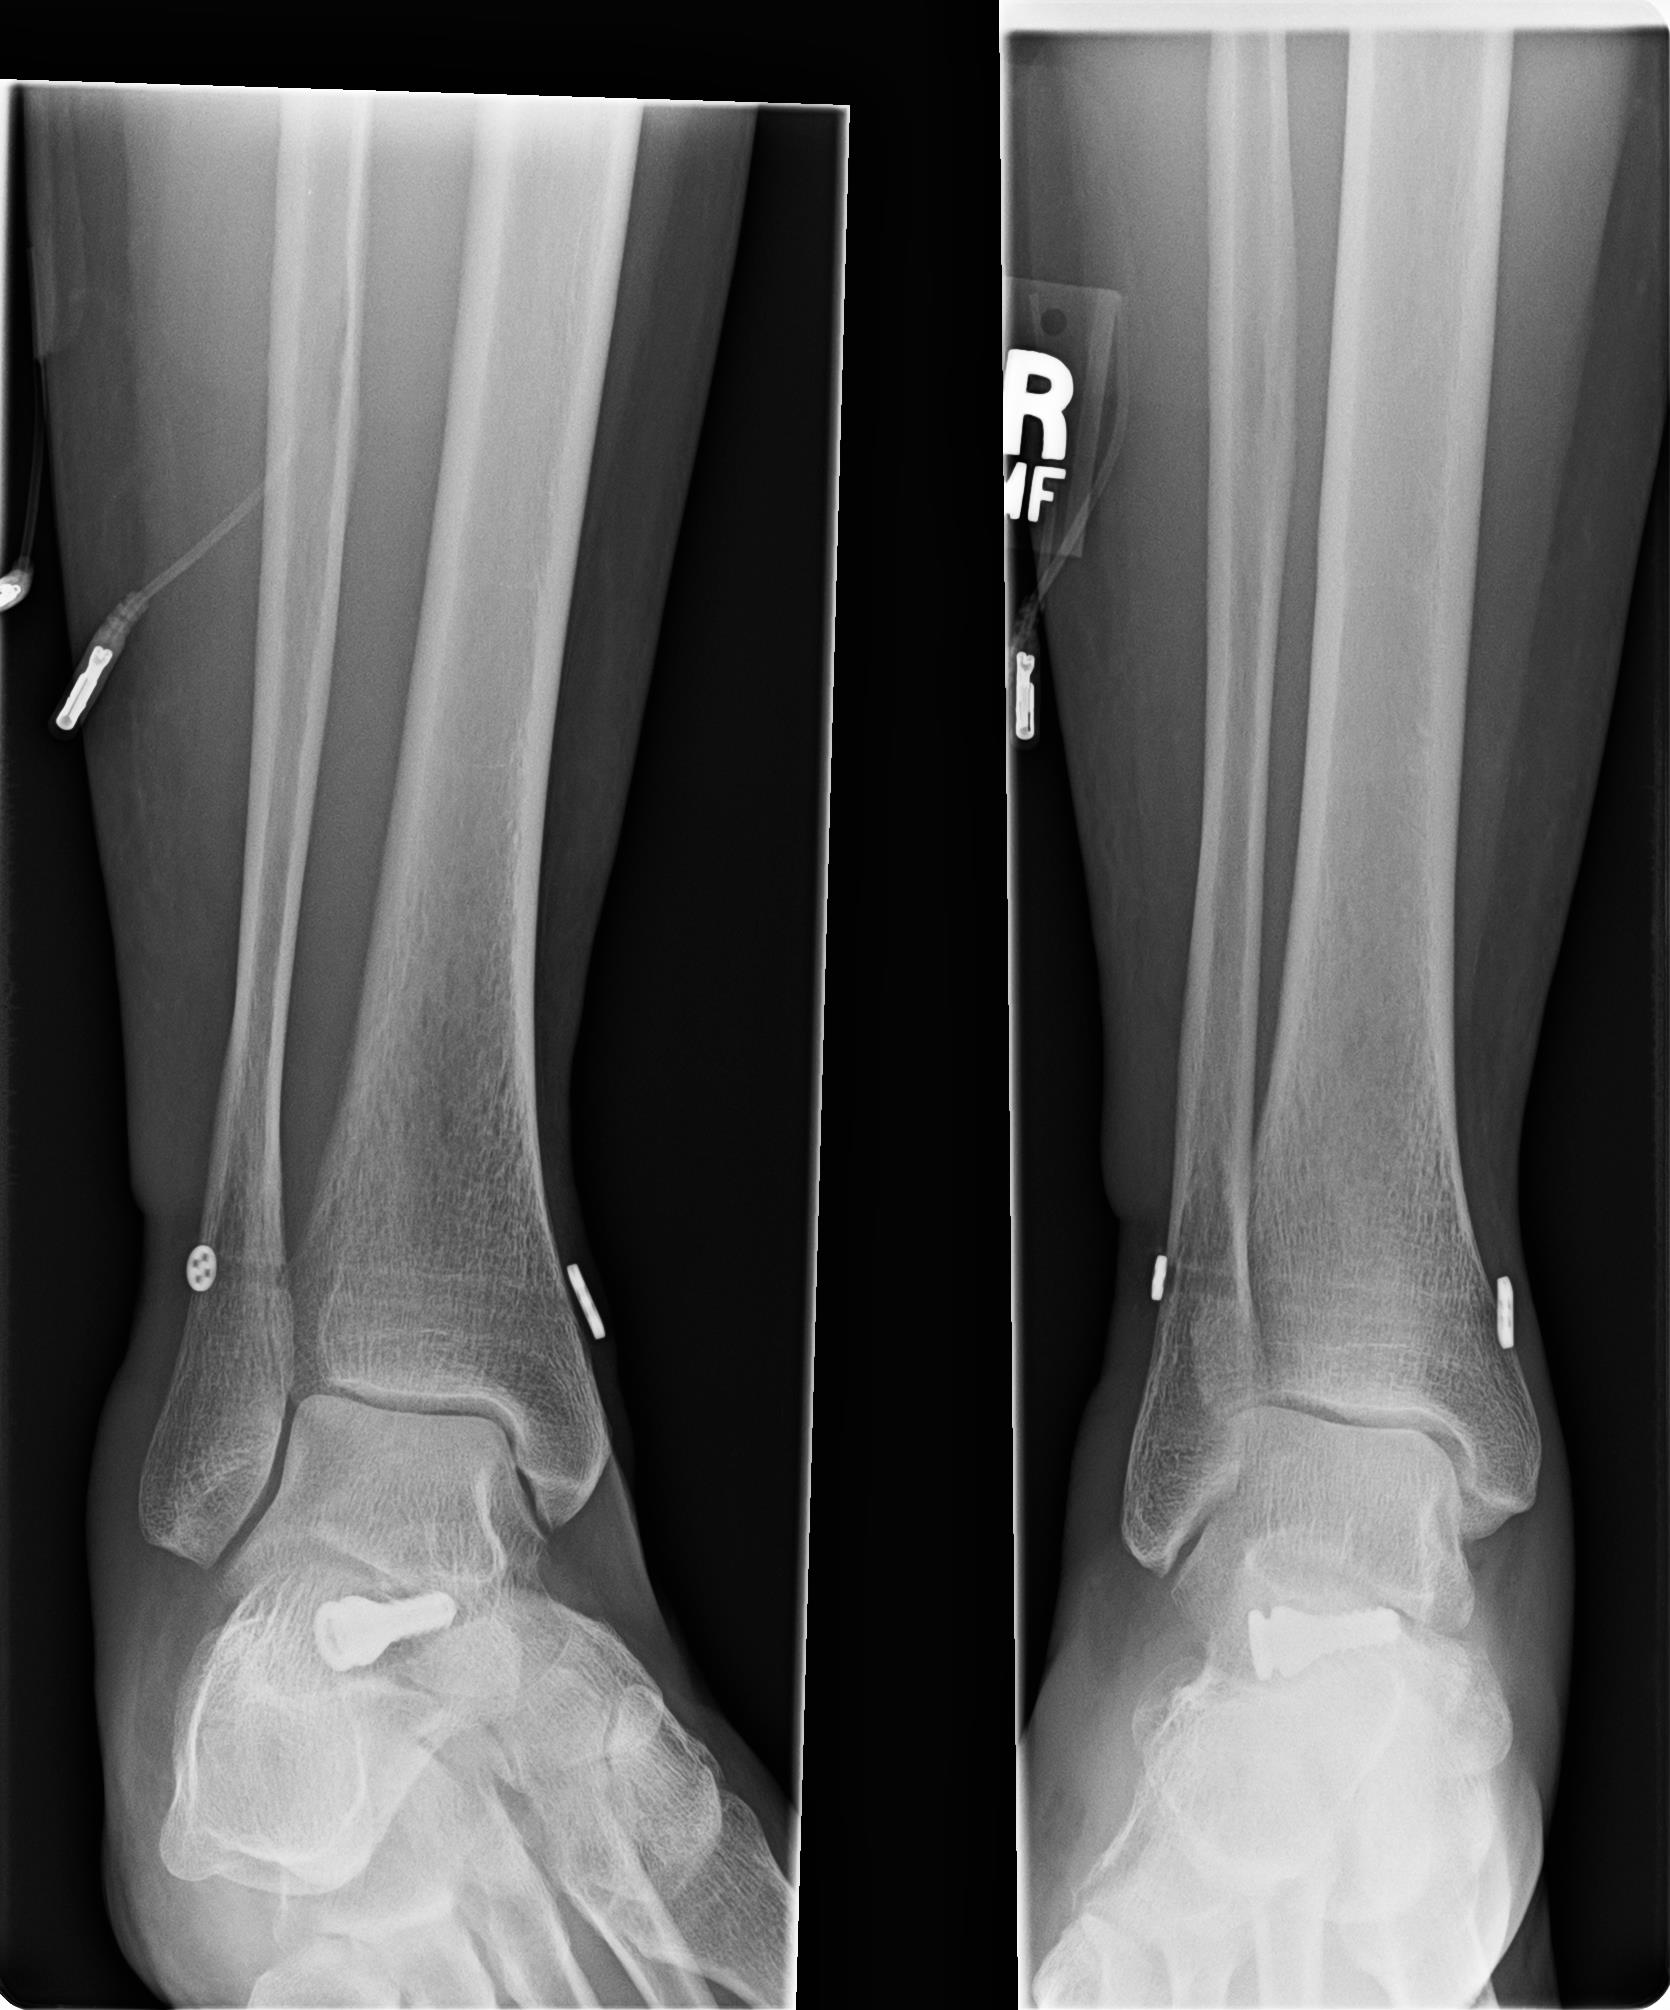

Post surgical X-rays are shown farther down in this blog. For those readers that want the surgical procedure details, please click each link for the PDF pages of the surgical report:

2. Dr. Main and I had discussed my right ankle joint still having some slight pronation and pain around the distal tib-fib. During surgery after doing the proximal fixations and tightening of the proximal syndesmosis, he checked the distal syndesmosis and it still showed some slight instability. He therefore went ahead and placed another Arthrex TightRope Fixation into the distal tib-fib of the ankle. All the fixations can be seen in the X-rays below in this blog.

Monday, 3-31-14— First Follow up appointment at 4 days since surgery. Post surgical x-rays taken of my right lower leg and ankle at Dr. Main’s office (click on photos to enlarge):